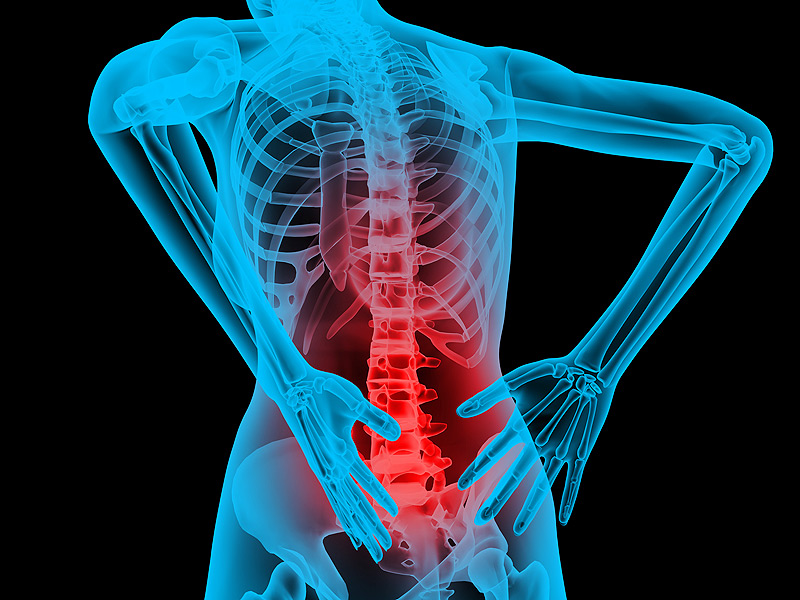

Lower back pain is experienced by us on a daily basis. We come home from a long hard day at work and our backache is just too much to handle. Our solution to end this back pain is to put some ice on it, or a hot water bottle and pop in some panadol to make us feel better. We tend to gravitate towards instant relief other than long term results.

Your back pain might be serious, and you need to get proper back pain treatment for that. We all feel back pain everyday or every other day. The excuses we give are “I worked too much today”, “The exercise was pretty tough today”, Only a few of us take this seriously and visit the doctor. When you visit the doctor you cannot identify the intensity of back pain.

Your pain in the back can be in the vertebrae, intervertebral discs, the ligaments or muscles of the back. Other effects that can also make you feel tired and helpless are kidney stones, disc prolapse, heart failure or osteoarthritis.

Causes of Lower Back Pain